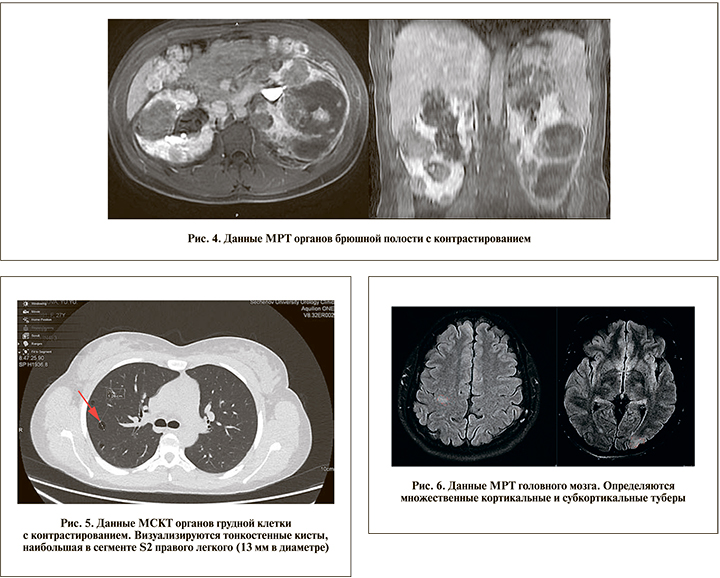

По данным МРТ, признаков продолжающегося кровотечения нет (рис. 4).

Данные МСКТ грудной клетки с контрастированием (04.07.2019): в паренхиме обоих легких прослеживаются одиночные мелкие (до 3 мм) очаги уплотнения, а также множественные разнокалиберные тонкостенные кисты – наибольшая в сегменте S2 правого легкого (13 мм в диаметре) соответствует проявлениям ЛАМ (рис. 5). Признаков пневмо- или хилоторакса не выявлено.

При МРТ головного мозга (25.06.2019) определялись множественные кортикальные и субкортикальные туберы (рис. 6); признаков СЭГА не выявлено.